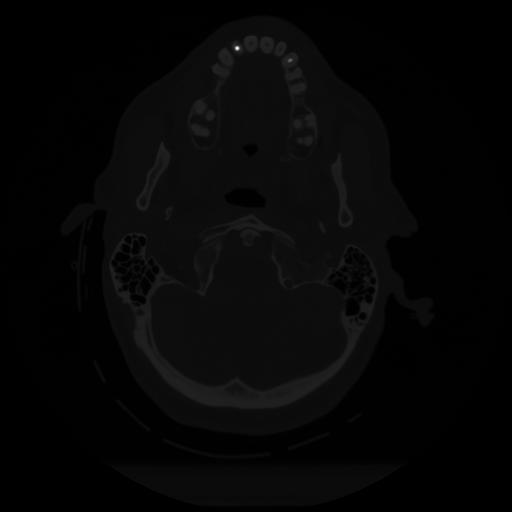

12 P.BLANDAS,,Vol,0.5,P.BLANDAS,,